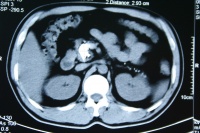

3.超声及CT检查

胰结石的敏感性在90%以上。若再结合CT检查阳性率尤高。CT检查对胰腺癌的诊断可提高阳性检出率当胰石症和并发胰癌时可见胰腺有钙化、假性囊肿、胰腺管扩张、胰腺外形不规则、局限性胰腺肿大、胰周脂肪消失等。